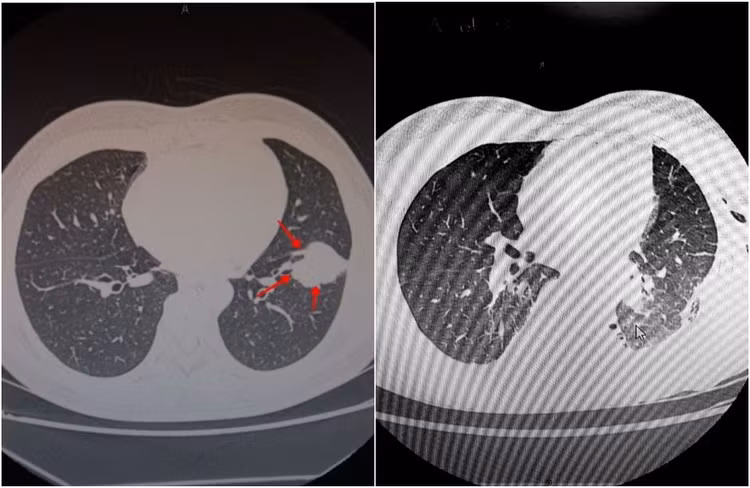

Kết quả chụp cắt lớp vi tính cho thấy, nhu mô thuỳ dưới phổi trái của người bệnh có khối u đường kính hơn 4cm. Sau khi sinh thiết đánh giá, các bác sĩ chẩn đoán bệnh nhân bị ung thư thuỳ dưới phổi trái, xâm lấn thuỳ trên phổi trái, được chỉ định phẫu thuật nội soi lồng ngực cắt u kết hợp hoá xạ trị để đạt được kết quả điều trị tốt nhất.

Hình ảnh chụp cắt lớp khối u phổi ác tính của bệnh nhân S. trước và sau khi phẫu thuật. |

Hình ảnh chụp cắt lớp khối u phổi ác tính của bệnh nhân S. trước và sau khi phẫu thuật.